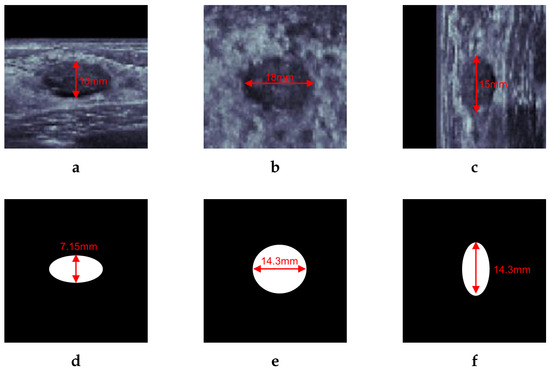

An example of a template mask is shown in Figure 4 with a sampled breast cancer. Figure 4a–c show transverse, coronal, and sagittal views of the center of a breast lesion. With lesion diameters of 10 mm, 18 mm, and 15 mm on each axis, the average diameter was 14.3 mm. The centroid of the template mask is located in the same position as the center of the lesion. Since the lesion has a ‘parallel’ feature of orientation, the positive area shrinks in the skin-perpendicular direction, obtaining the shape of an ellipsoid whose semidiameters are one of 7.15 mm and two of 14.3 mm, as shown in Figure 4d–f.

Figure 4. Example of template mask. (ac) Slice image of transverse, coronal, sagittal view of breast cancer on ABUS including diameters of each axis. (df) template mask matched to (ac). Using average diameter of the lesion, the mask label has two of equal semidiameters of 14.3 mm and 7.15 mm semidiameters, which is the half-length of the other diameters due to parallel orientation property.